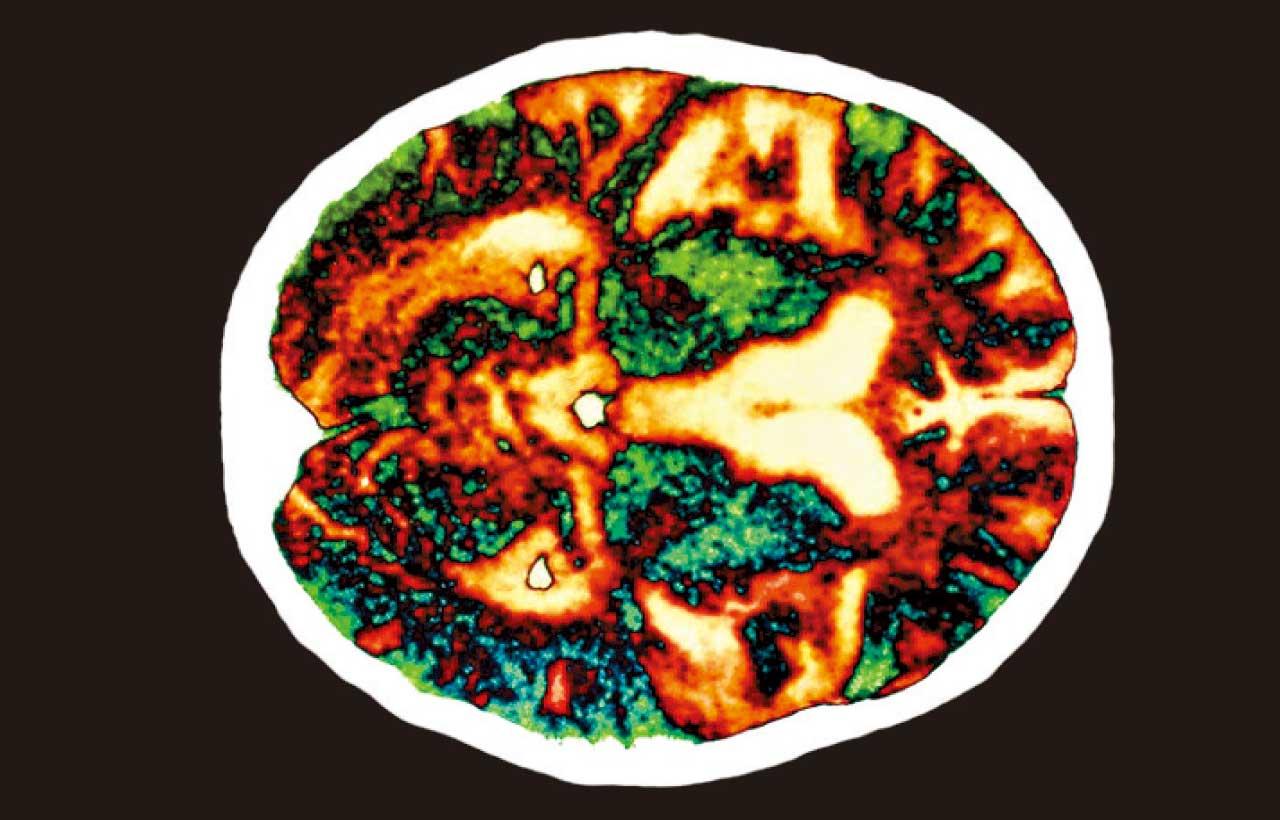

阿茲海默症患者腦部掃描影像。(互聯網)

阿茲海默症成因是腦細胞出現病變,產生澱粉樣蛋白,形成斑塊積聚於大腦,破壞腦細胞之間的連接,上述病例懷疑與兒時曾接受生長荷爾蒙治療有關。當兒童生長緩慢、身形太矮,治療方法之一是注射生長荷爾蒙,而英國等地於1950至80年代注射用的生長荷爾蒙,是從大量屍體的腦部採集。